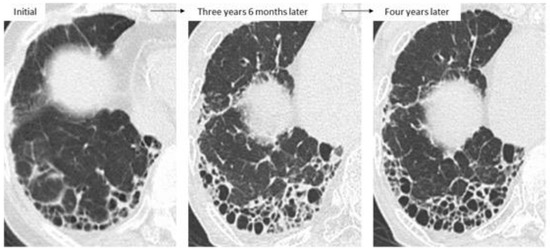

4.2. Disease Behavior

4.3. Predictors of ILD Progression and Prognostic Factors